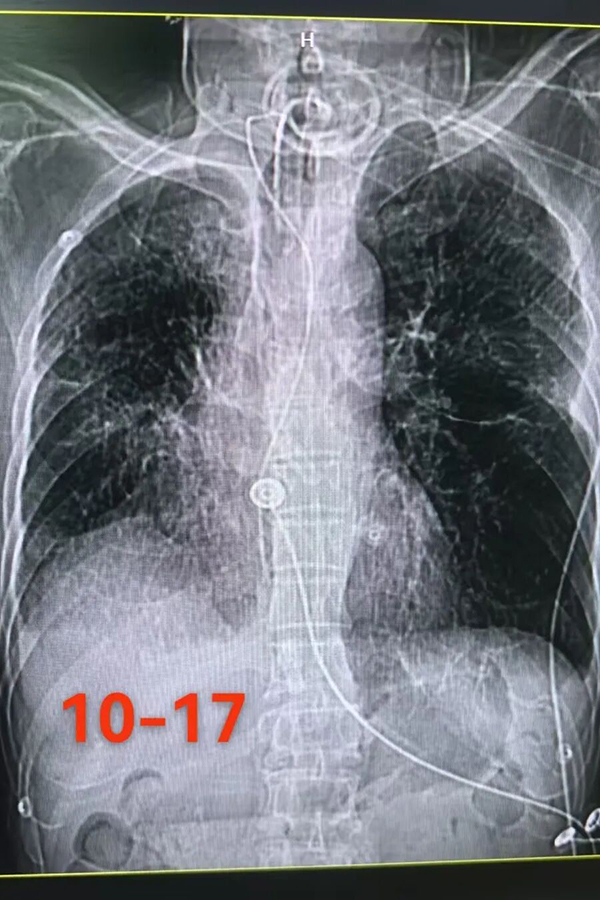

今年8月,64岁的老李(化名)因反复咳嗽,在当地医院确诊为“肺炎、气胸”。尽管经过了一个多月的积极治疗,病情却并未出现明显的好转。随后,老李突发高热、呼吸衰竭,被紧急送入ICU。看着病床上日渐虚弱的父亲,李先生和母亲内心充满了煎熬。

9月29日入院时,老李的情况十分危急。神志欠清,气管切开处连接着有创呼带领团队迅速对老李的病情进行了全面评估和深入研讨,制定了“个体化、全方位”的精准救治方案:

在原有基础上调整抗感染方案,精准打击致病菌。同时,通过支气管镜检查+肺泡灌洗,深入气道清理分泌物,有效减少了感染源。

针对气胸和呼吸衰竭问题,团队精准实施胸腔闭式引流,配合严谨的气道管理策略,确保呼吸通畅。

在RICU团队的日夜守护与精心照料下,入院一周后,老李的感染指标明显回落,体温恢复正常,胸腔闭式引流管也顺利拔除。这“第一关”的通过,让所有人看到了曙光。

随后半个月,在早期呼吸康复训练的介入下,老李的呼吸功能迎来了质的飞跃。经团队专业评估达标后,他成功摆脱了有创呼吸机,改用经鼻高流量湿化氧疗,并平稳地从RICU转入了普通病房,完成了治疗路上的关键跨越。